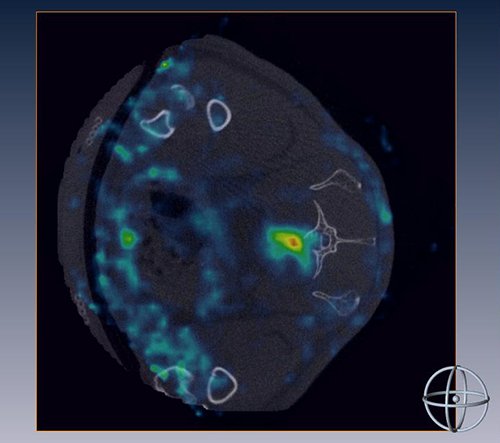

Human stem cells, isolated from bone marrow, home to a fractured and osteoporotic vertebra.